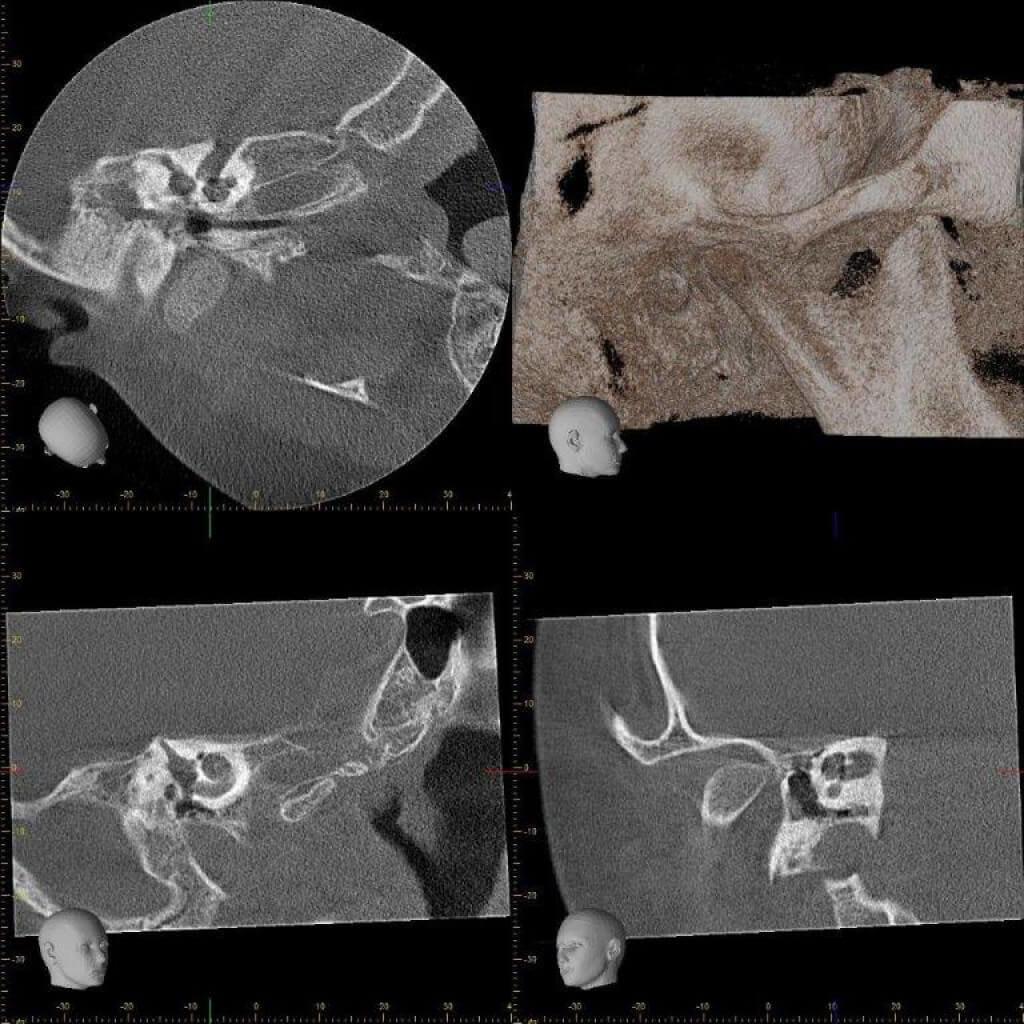

КТ анатомия сосцевидного отростка: особенности и показания

Раздел: Галерея прозрений